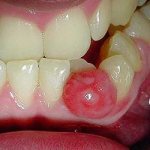

Киста во рту — фото

Впоследствии скопление гноя распространяется дальше, разрушая кость и образуя своеобразную полость, которую стоматолог видит на рентгене пораженного зуба. Образующийся гной постоянно стремится выйти наружу путем наименьшего сопротивления. При отсутствии лечения инфекция, постепенно рассасывая кость, сформирует ход от корня зуба в полость рта, проходя через кость и десну. На десне станет заметно выпуклое образование, часто заполненное красноватой или бело-желтой жидкостью. Затем стенка десны лопнет и гной изольется наружу.

- образование округлого элемента на десне, содержащего жидкость желтоватого или красного цвета;